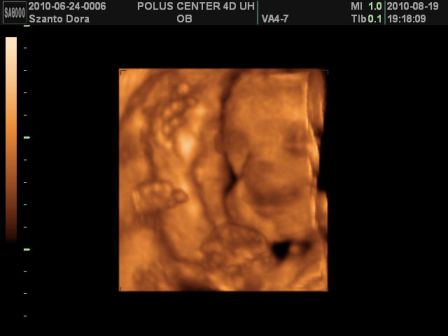

Basszus! Hívtam a kórházat, kiderült a dokim szabin, csak jövő héten szerdán lesz, de menjek be mindenképpen az ügyeleteshez! Na, anyuval felkerekedtünk és irány a kórház. Először csináltak egy uh-t! Dani épp fent volt és akkorákat rúgdalt, h patogott a nőci kezében a vizsgáló kütyü!

Megint nagyobbra mérték egy héttel, szóval továbbra is tartjuk a november elejét, mint születés. És farfekvéses a drágám egyelőre...

Viszont, most már 1360g volt a súlya az 1 héttel ezelőtti 1160g-hoz képest!